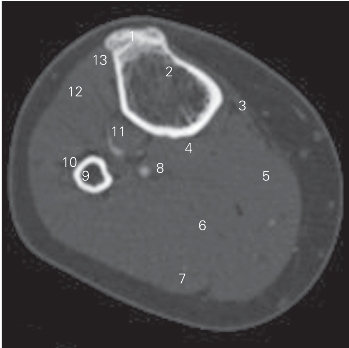

图5-32 经小腿上份的横断层CT图像(骨窗)

1 胫骨粗隆 tibial tuberosity 2 胫骨 tibia

3 缝匠肌 sartorius 4 趾长屈肌 flexor digitorum longus

5 腓肠肌内侧头 medial head of gastrocnemius

6 比目鱼肌 soleus

7 腓肠肌外侧头 lateral head of gastrocnemius

8 腓神经 tibial nerve 9 腓骨 fibula

10 腓总神经 commer pernoneal nerve 11 胫骨后肌 tibialis posterior

12 趾长伸肌 extensor digitorum longus 13 胫骨前肌 tibialis anterior